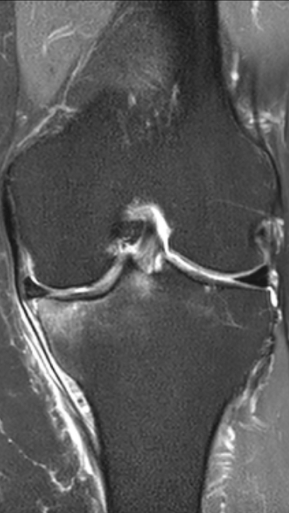

Асептический некроз коленного сустава

4 процедуры ФДТ, 9 процедур MBST, 15 процедур ИПМТ

Параметры изменяются в зависимости от процедуры